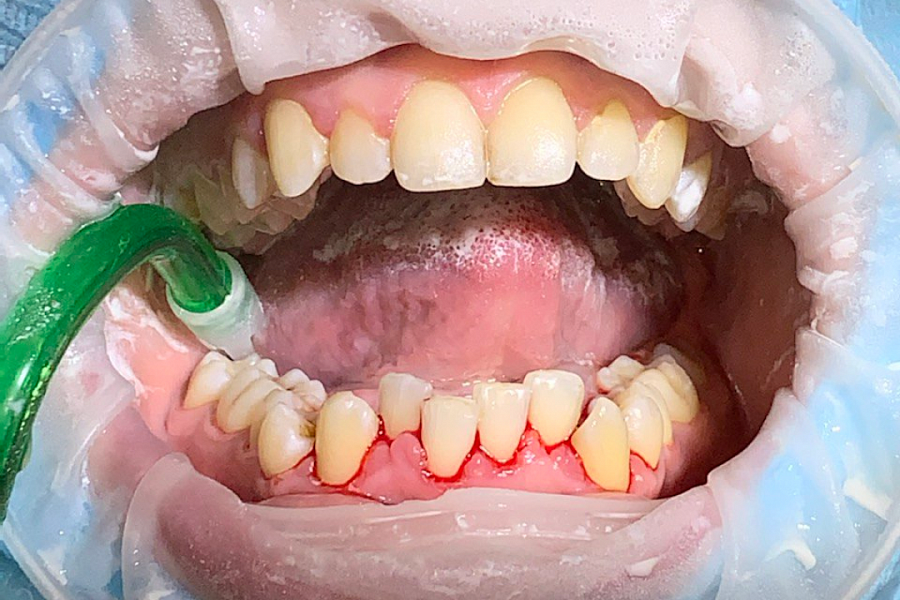

Фото до/после говорят сами за себя

Профессиональная гигиена полости рта; снятие зубных отложение, как наддесневых, так и поддесневых; закрытый кюретаж пародонтальных карманов; чистка Air-Flow; удаление налета курильщика, ручная чистка и чистка ультразвуком; обучение профессиональной гигиене полости рта, демонстрация пациенту правильных методов чистки зубов; определение гигиенических индексов, подбор индивидуальных средств гигиены; отбеливание зубов.